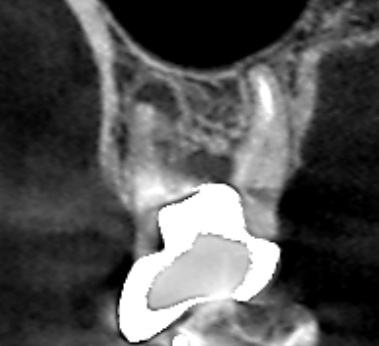

6カ月後の経過観察時の冠状断のCT画像です。適切なパーフォレーションリペアによって根の分岐部にあった膿の影が消え、歯槽骨が再生しています。